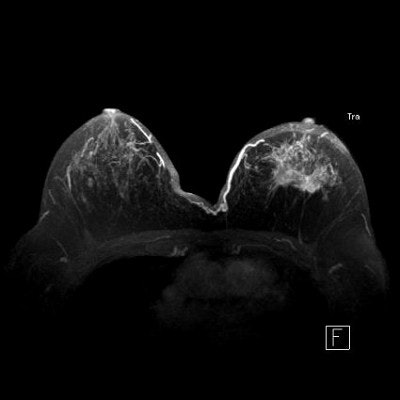

For lobular cancer diagnosis, Porter relies on a series of MIPs acquired over time to allow gadolinium contrast to leak, pool, and enhance tumor vessels.

The diffuse infiltrative nature of lobular carcinoma makes it difficult to detect. Two-minute (top), four-minute (middle), and thin-MIP (below) views demonstrate contrast enhancement in tumor tendrils over time. Images courtesy of Dr. Bruce Porter, First Hill Diagnostic Imaging.